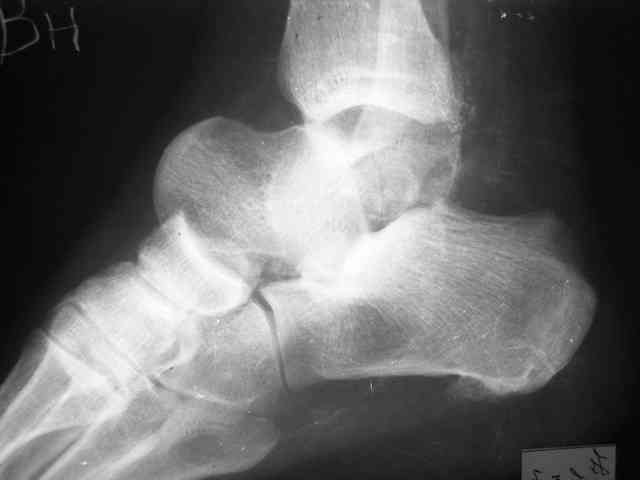

Re: Редкое повреждение - полный вывих тарана!

Уважаемый Александр! Как обещал представляю Р-граммы и операционные фото.

Ваши (лично ваши) рекомендации - астрагалэктомия-аппаратный пяточно-большеберцовый артродез с одновременным удлинением голени - правильно?

А так инфекция куда денется, или ПБА изничтожит ее в м/тканях? Она там уже полгода живет. Я думаю стабильная фиксация - лучшая профилактика инфекционных осложнений. Кстати была у нас больная с посттравматическим деф. артрозом г/стопного сустава и остеомиелитом внутренней лодыжки - ей сделали костно-пластический артродез по Кловарду - инфекция затихла, анкилоз наступил за 3 мес (больной 65 лет).